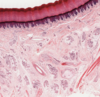

What is shown by the letters in the high magnification of keratinised squamous epithelium?

b - stratum spinosum

c - stratum granulosum

e - stratum corneum